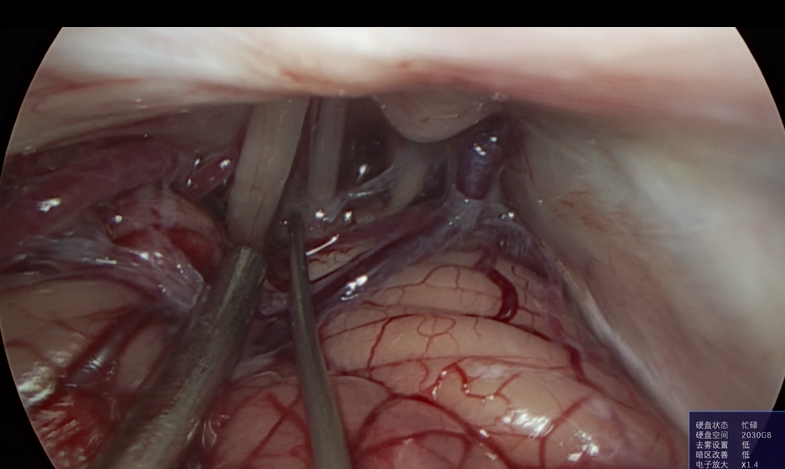

神经外科垂体瘤手术